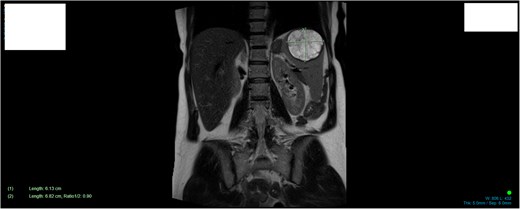

A 34-year-old woman presented to the Emergency Department with upper abdominal pain of a few days’ duration with associated nausea. She had no past medical or surgical history. She was hemodynamically stable. Routine blood work and beta human chorionic gonadotrophin were normal. Initial investigation included a Pelvic Ultrasound Scan which showed a complex cystic lesion on the superior aspect of the spleen measuring 64 × 62 × 62 mm. Further investigation with serial imaging including Commuted Tomography (CT), Magnetic Resonated Imaging (MRI) and Proton Emission Topography (PET) demonstrated a cystic lesion of the upper pole of the spleen with an enhancing mural nodule and radiological appearance of a dermoid cyst (Figs 1 and 2). This nodule was found to have low grade avidity on PET scan. The splenic vasculature demonstrated a magistral arrangement on contrast enhanced CT. Hydatid Serology was negative.

MRI demonstrating size and anatomical location of splenic lesion coronal plane.